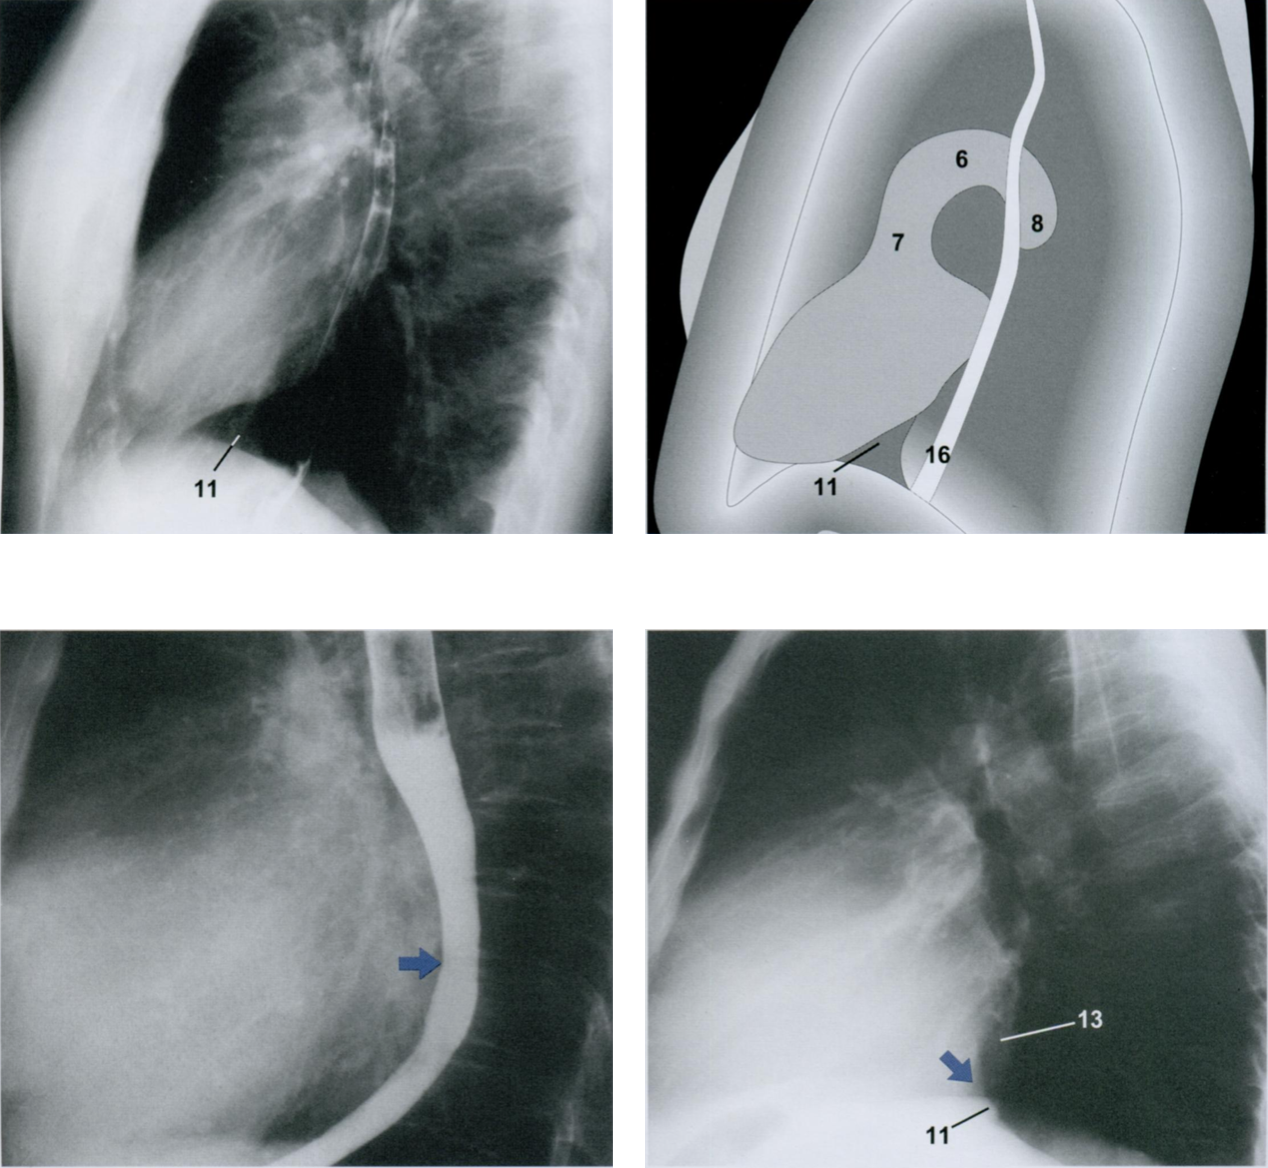

На рентгенограмме в боковой проекции после приема внутрь контрастного препарата можно установить характер дилатации левого предсердия. При этом пищевод заметно отклоняется от своего нормального (первые два снимка) вертикального хода - появляется выпуклость кзади на уровне левого предсердия (второй и третий снимки). Кроме того, при хроническом митральном стенозе определяются признаки венозного полнокровия из-за «блокирования» крови в малом круге кровообращения.

Возникающее при этом расширение левого желудочка (косая стрелка вниз) можно оценить по сужению ретрокардиального пространства (13) на рентгенограмме в БП (четвертый снимок).

Это сужение возникает на более низком уровне (третий снимок), чем при дилатации левого предсердия. В результате исчезает треугольник НПВ (11), обнаруживаемый на предыдущей рентгенограмме, что является ранним симптомом начинающейся дилатации левого желудочка.